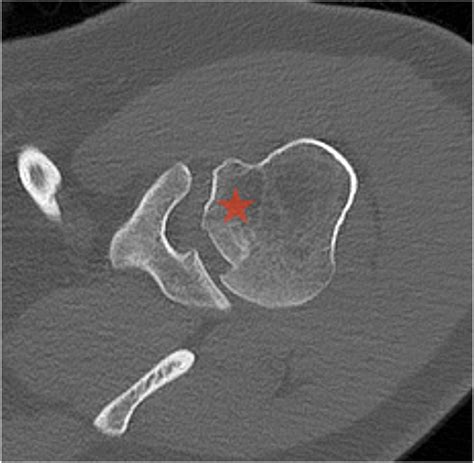

The shoulder is a ball-and-socket joint, designed for a vast range of motion. However, this flexibility comes at the cost of stability. When an anterior shoulder dislocation occurs, the humeral head is pushed forward and out of the socket. In many cases, the bone travels until it strikes the glenoid rim. Because the bone of the humeral head is relatively soft, the harder bone of the glenoid rim acts like a stamp, creating a “divot” or notch in the humeral head.

This indentation is the Hills Sachs lesion. It is important to note that these lesions are highly prevalent in patients who experience recurrent shoulder instability. Once the bone has been dented, the "locking" mechanism of the shoulder is compromised, making it easier for the joint to dislocate again in the future. This creates a cycle of instability that often requires medical intervention to correct.

CT Scan The gold standard for quantifying the amount of bone loss in the humeral head and glenoid.